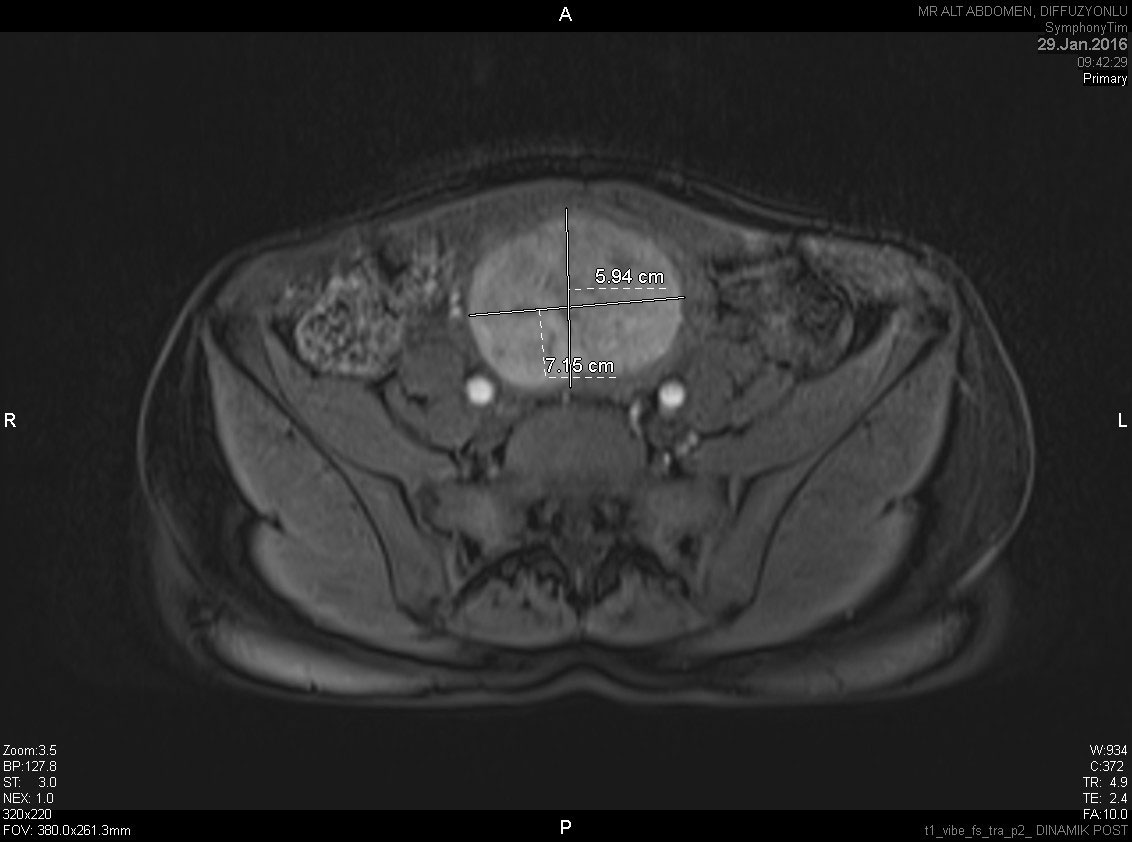

Böbrek Anjiyomyolipom

Böbrekte gelişen iyi huylu, büyük boyutlara ulaşabilen bir kitle olup kanama ...